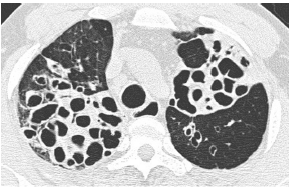

支气管扩张

377x338 - 184KB - PNG